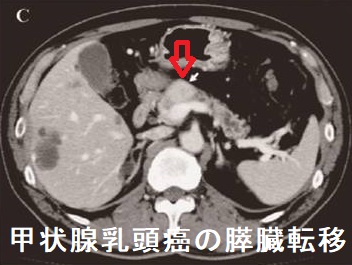

甲状腺乳頭癌の膵臓転移 造影CT(日本消化器外科学会雑誌.2011;44(4):442-448)

甲状腺乳頭癌に対し甲状腺全摘10年後、頸部リンパ節再発を認め、同時にFDG-PET/CTで集積し、造影CTで造影効果のある膵頭部腫瘍を発見。不思議にも他臓器転移なく、膵内分泌腫瘍の可能性も考えられたが、膵頭十二指腸切除術後の病理組織学的検査で甲状腺乳頭癌の膵転移が確定(日本消化器外科学会雑誌.2011;44(4):442-448)。